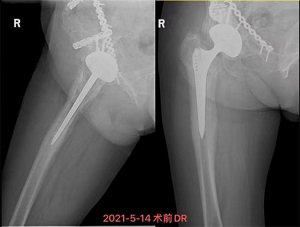

“出院回家了!”5月28日,我院关节骨病科病房传出严爷爷阵阵爽朗的笑声。年近古稀的严爷爷早在2005年因摔伤致股骨颈骨折在某医院做了右人工全髋关节置换手术。2019年初,严爷爷愈发觉得右髋关节隐隐作痛,且疼痛越来越重,到2020年底,连膝关节也痛得没法自如活动了,出现了明显的跛行。

5月13日,饱受关节疼痛困扰的严爷爷在家人陪同下到我院就诊并入住关节骨病科。董克芳主任团队在仔细评估讨论后,制定了详细手术方案,并于5月21日为严嗲嗲进行了右人工髋关节翻修术,术后当日即指导其开始进行功能锻炼,1周后,严爷爷可下地行走,关节疼痛感也没了。28日,主管医生林少如反复叮嘱老人家一些注意事项后,严爷爷在家人陪同下出院回家了。